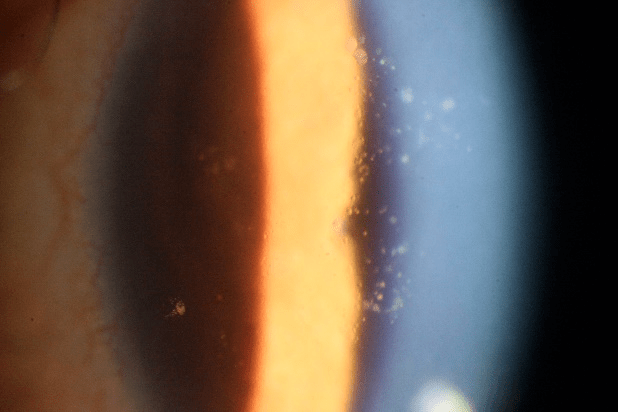

7.1虹膜反射

角膜后沉着物

操作要点

• 光源亮度:中等至最强亮光

• 裂隙宽度:3-4mm细窄至微宽

• 裂隙夹角:0°~15°,可调

• 放大倍率:10x或者更高倍

• 光线照射在虹膜面上,使虹膜反射光照射在角膜后面,在光亮背景下观察角膜上的不透明病变

• 观察:角膜上皮水肿、空泡,细小角膜后沉着物等